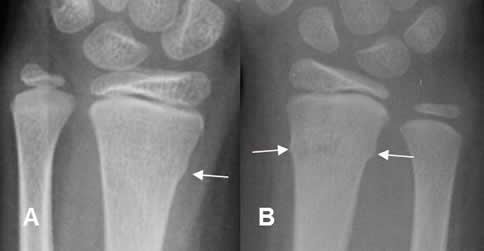

Fig 63 B. Fractura en torus.

A y B: Rx AP. Fractura en torus del radio distal. En la proyección de control, se identifica imagen densa en el lugar de la cicatrización.